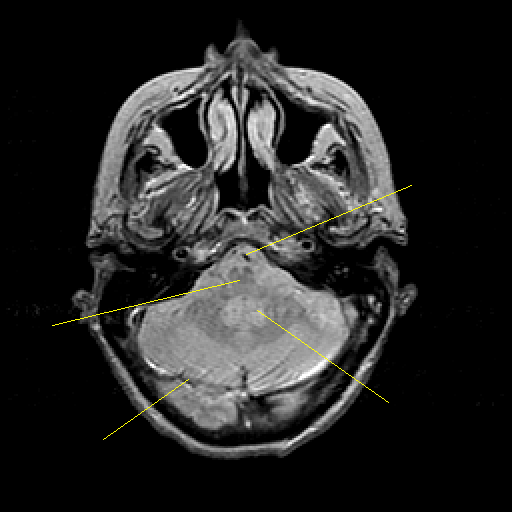

Proton density-weighted structural MR: Slice 12

Pointers

Labeled